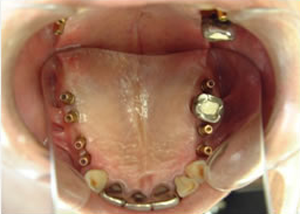

4.下14本最終の冠をかぶせたところ-上から(鏡)

-正面-下14本の最終の冠をかぶせたところ